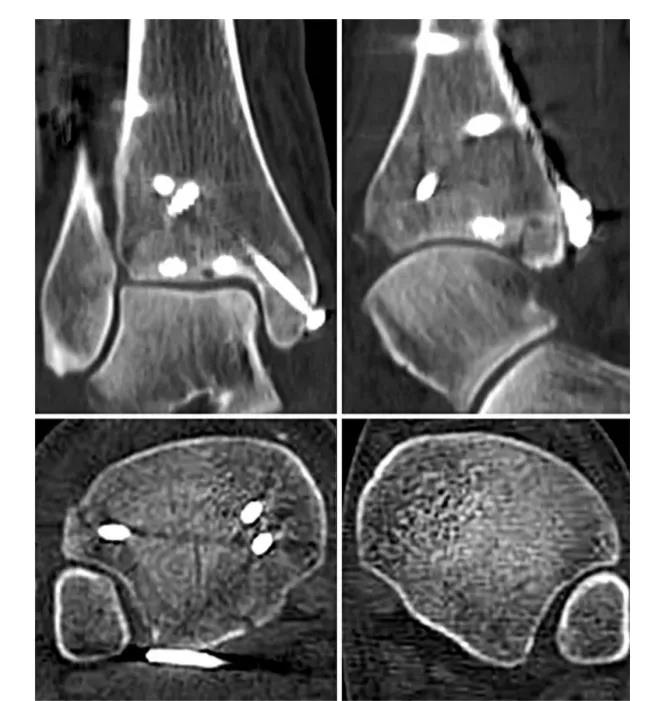

⑧ 复位后典型病例图。